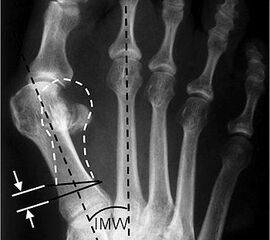

Abbildung 1

• Röntgenaufnahme des Fußes unter Belastung in d.p., schräg und seitlichem Strahlengang.

• Beurteilung des Intermetatarsalwinkels (IMA) und des distalen und proximalen Gelenkwinkels (DMAA, PMAA) (Abb. 1).

• Planung der Korrekturosteotomie: 1 mm Plattensteg korrigiert etwa 2° Intermetatarsalwinkel.